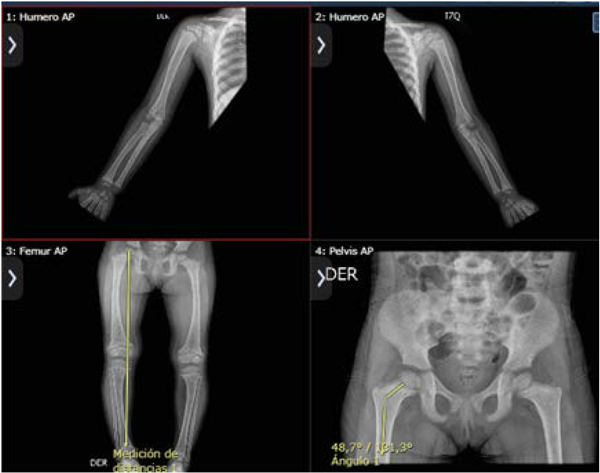

El carpograma reportó edad ósea por debajo de -2 de para la edad cronológica y las radiografías de huesos largos evidenciaron metáfisis distales de radio, cubito, fémur distal, tibia proximal en forma bilateral ensanchadas e irregulares con aspecto de "copa invertida", score raquitismo 8/10 (figura 2). Se confirmó diagnóstico de hipofosfatemia de origen renal por los resultados de la reabsorción tubular del fósforo (de 72 % anormal) y reabsorción máxima tubular de fosfato para el filtrado glomerular de 2.1 anormal, con función renal normal. Se descartó raquitismo carencial y síndrome de Fanconi como diagnósticos diferenciales. A la edad de 4 años y 6 meses llega el resultado de la prueba genética, que identificó una variante en el gen PHEX —posición: chrX:22.263.483, variante: C > T, con secuencia: p.Arg702*ENST00000379374, copias: heterocigosis (1 copia)—, lo que configuró una variante patogénica y se confirmó el diagnóstico de RHLX. Recibió tratamiento farmacológico con solución de fosfato para suplencia de fósforo a dosis de 60 mg/kg por día y calcitriol. En la actualidad, continúa en seguimiento por nefrología y endocrinología pediátrica con buena evolución clínica.

Figura 2. Anomalías en huesos largos

Hallazgos: metáfisis distales de radio, ulna, fémur distal, tibia proximal en forma bilateral ensanchadas e irregulares con aspecto de "copa invertida".

Ángulo metafisodiafisiario de 10° bilateral, normal.

Ángulo cérvico diafisario derecho de 131° y el izquierdo de 126°.

Tubulización de huesos largos normal con adecuado grosor cortical.

Genu varu bilateral según eje mecánico.

No hay reacción perióstica, lesiones líticas o blásticas.

Alerones iliacos de aspecto normal, conservando la morfología del anillo pélvico y los

agujeros obturadores.

Morfología normal de ambas caderas.

Fuente: radiografías tomadas de la historia clínica de la paciente.